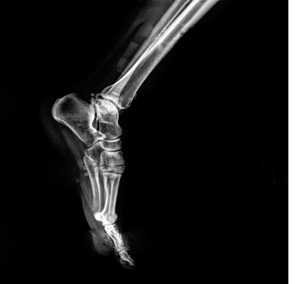

Рентгенологическое исследование

Для диагностики повреждения сустава Шопара делают рентген, КТ и МРТ. На передне-задней рентгенограмме определяют величину пяточно-кубовидного угла. Проводят одну касательную к наружному краю кубовидной кости и вторую касательную к наружному краю пяточной кости. В норме угол между касательными колеблется в пределах от 0 до 5°. Увеличение угла свидетельствует о нарушении стабильности пяточно-кубовидного сочленения. КТ во фронтальной и сагиттальной плоскостях позволяет выявить дефект суставных фасеток, смещение костей при вывихе и фрагментацию костей при переломе. КТ, по сравнению с рентгенографией, является более информативным методом диагностики. МРТ позволяет выявить дефекты отдельных связок.

Рис. 6. Отрывной перелом по тылу таранной кости на границе с суставом Шопара

Рис. 7. Перелом кубовидной кости по передней поверхности

Рис. 8. Переломо-вывих в суставе Шопара

Рис. 9. Переломо-вывих в суставе Шопара